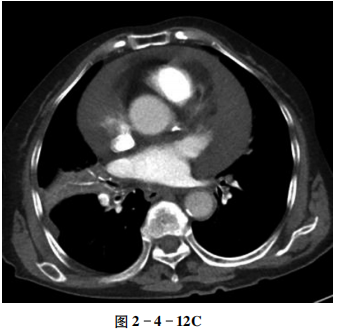

【CT征象】

心包内见大量液体密度影,密度均匀,最厚处厚度约33 mm(图2-4-12A);增强扫描无强化(图2-4-12B、C)。两下肺动脉内可见充盈缺损。

心包腔内均匀液性低密度影。

心包腔厚度增加,其内可见液体密度影;一般心包腔内厚度5~15 mm为少量心包积液,15~25 mm为中等量心包积液,25 mm以上为大量心包积液;心影可正常或增大,局部异常膨凸或成角,心缘不规则。